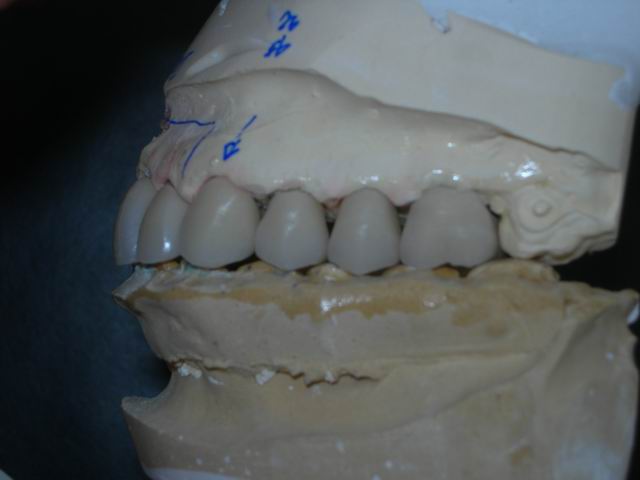

Modelo de transferência após aplicação/modelagem cerâmica sobre copings (vista direita)

Modelo de transferência após aplicação/modelagem cerâmica sobre copings (vista esquerda)

Modelo de transferência com cerâmica aplicada pronta para a prova e ajustes em boca